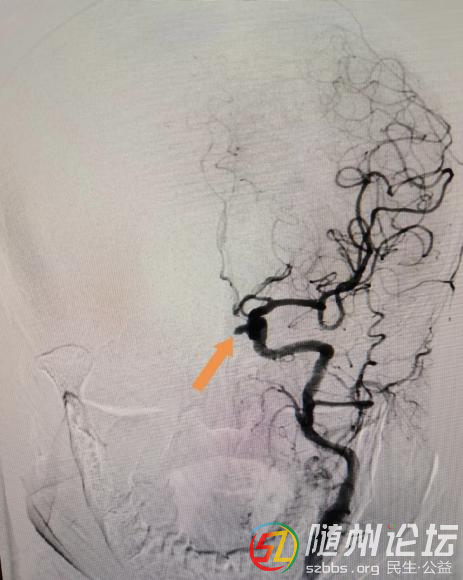

曾都醫(yī)院:精準栓塞,守護大腦--介入下動脈瘤栓塞術(shù)為生命護航 近日,在武漢大學中南醫(yī)院但畢堂教授指導下,隨州市曾都醫(yī)院神經(jīng)內(nèi)科與介入科、麻醉科緊密配合,成功完成了4例介入下顱內(nèi)動脈瘤栓塞術(shù),其中2例為動脈 ...